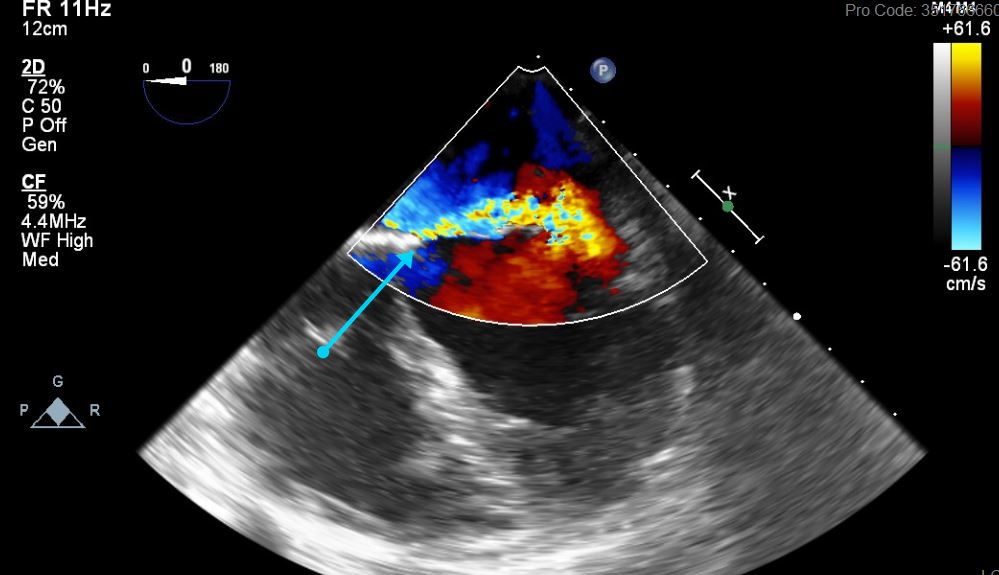

Puzzle 50 annotated

What's the Diagnosis?